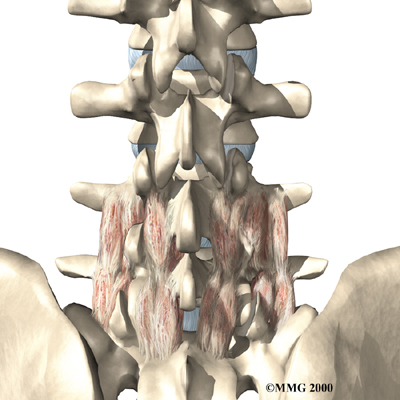

The human spine is formed by 24 spinal bones, called vertebrae. Vertebrae are stacked on top of one another to form the spinal column. The spinal column gives the body its form. It is the body's main upright support. The section of the spine in the lower back is known as the lumbar spine.

The lumbar spine is made up of the lower five vertebrae. Doctors often refer to these vertebrae as L1 to L5. These five vertebrae line up to give the low back a slight inward curve. The lowest vertebra of the lumbar spine, L5, connects to the top of the sacrum, a triangular bone at the base of the spine that fits between the two pelvic bones. Some people have an extra, or sixth, lumbar vertebra. This condition doesn't usually cause any particular problems.